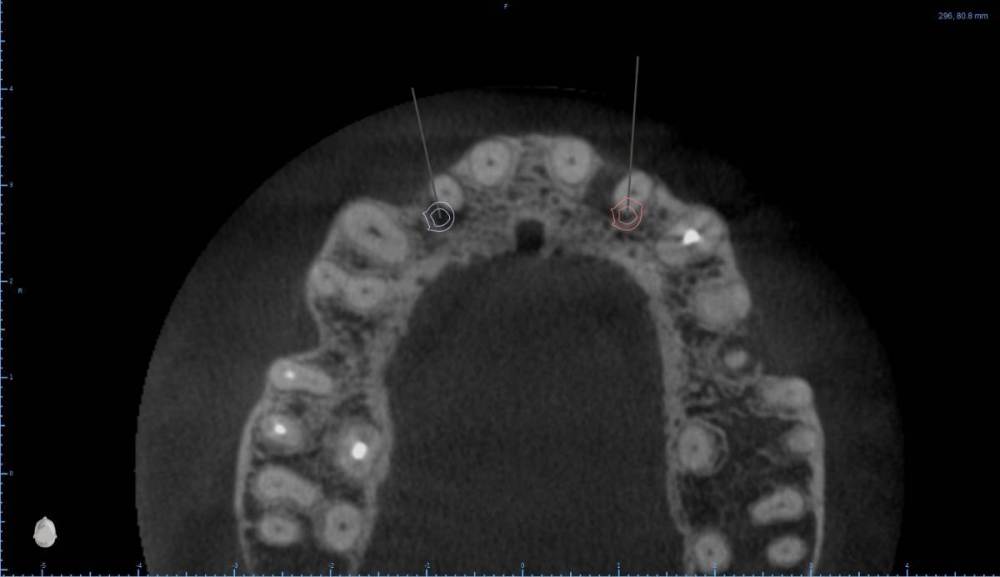

Женька Опубликовано 6 августа, 2022 Поделиться Опубликовано 6 августа, 2022 В общем планируется большая (по крайней мере для меня) работа. Вот такой товарищ у нас. Делали бы НКР в области 2.5з? или поставили бы чисто по кости, а оголённый участок закрыли присыпкой и мембраной? Также вопросы по двойкам имеются. Бугор есть, сразу оговорюсь, правда только с одной стороны. Также не понятно пока "как его правильно готовить" этот бугор, чтобы закрыть такие дефекты вестибулярной пластинки. Скрины постарался нарезать по максимуму. Там ещё будет ортодонтия конечно же. Интрузии, движения всякие и тд) Да, знаю, что планировать без цифрового гипса неправильно, но что имею. Ссылка на комментарий

Irouil Опубликовано 6 августа, 2022 Поделиться Опубликовано 6 августа, 2022 Если будет ортодонтия, то не проще ли вытянуть двойки чтобы вырастить ткани? ИДР тут нужен основательный очень, винты придётся крутить тоже очень длинные В области премоляра не вижу смысла что-то графтить, если хочется чего-то натолкать - можно стружки со сверла упаковать в дефект, но имхо не обязательно. А если сместить винт небно и чуть аннулировать, преп только пилотным и дальше конденсировать... ну Вы поняли 1 Ссылка на комментарий